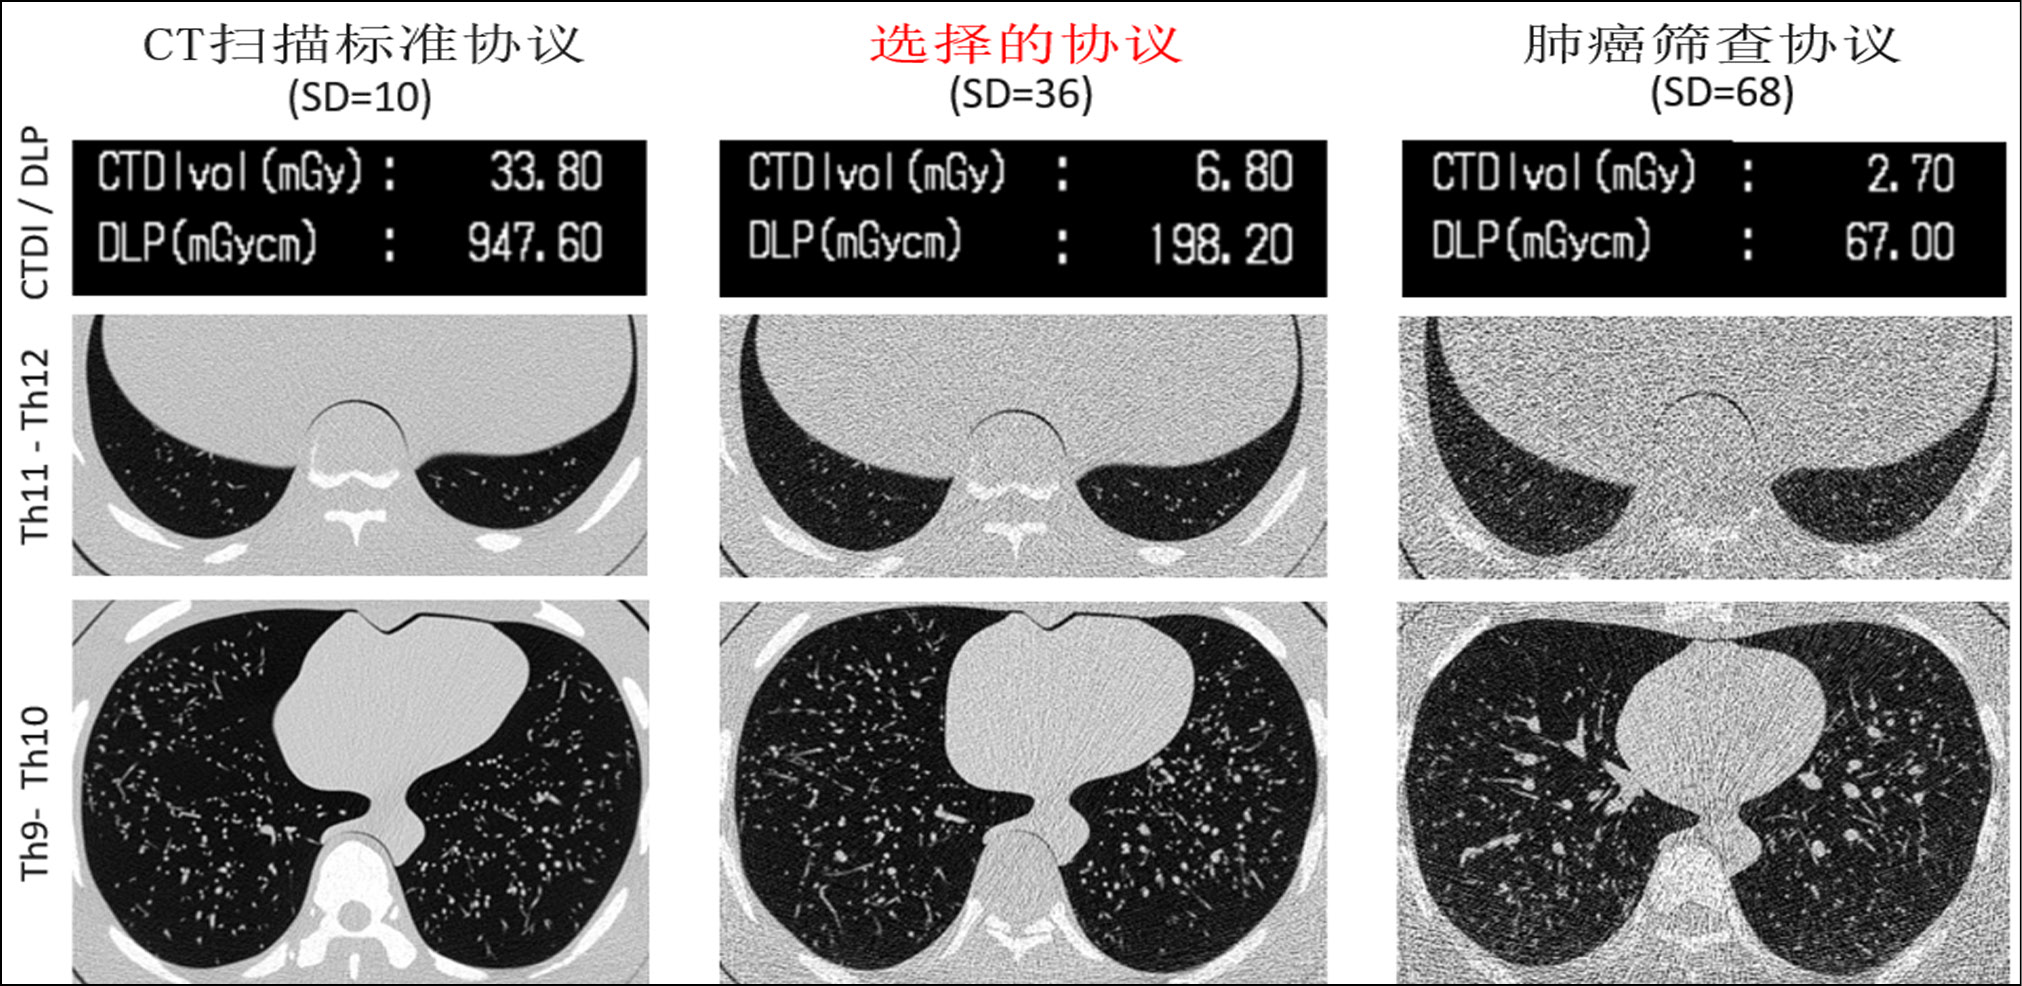

Interestingly, a parameter to be changed when optimizing the scanning protocol can be universal for various clinical tasks. Therefore, in LDCT for lung cancer screening, different groups of authors also changed the tube current [55, 56]. However, the development of a specialized LDCT protocol should be initiated with a study on a model object (phantom) to select the optimal method for reducing the exposure. For example, Gombolevsky et al. [57] developed the LDCT protocol for the diagnosis of COVID-19 using a phantom with thickening plates, while setting the automatic tube current control system (Sure Exposure 3D) to a sufficient level to detect ground-glass lesions with a maximum reduction in radiation exposure (SD = 36). A comparison of the protocol selected according to the results of the phantom study with standard CT and LDCT for lung cancer screening is shown in Fig. 1.

Figure 1. Comparison of a dedicated low-dose computed tomography protocol for COVID-19 (SD = 36) with standard and low-dose computed tomography for lung cancer screening. Data on radiation exposure and axial tomograms of the phantom at the level of the lower and middle zones of the lungs. Low-dose computed tomography for lung cancer screening was developed considering the need for radiation exposure limitation as preventive measures according to SanPin (disease control and prevention standards) and has the lowest signal-to-noise ratio. The proposed protocol for low-dose computed tomography for COVID-19 considers the densitometric characteristics of ground-glass lesions with a significant reduction in radiation exposure.